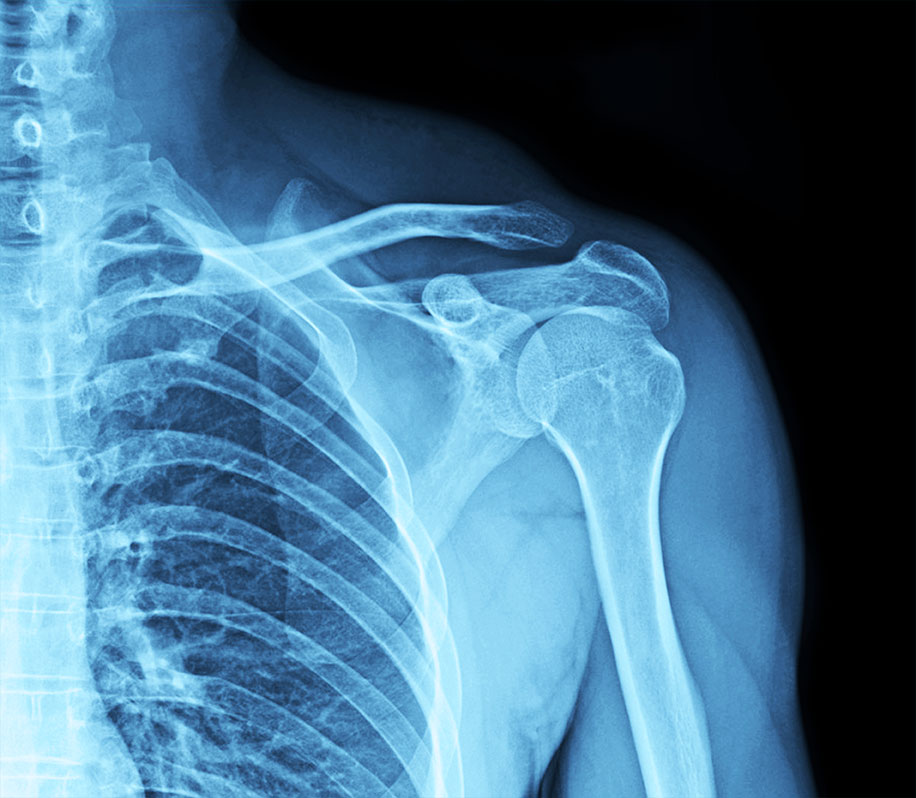

2. OSTEOPOROSIS AND BONE HEALTH

Estrogen is crucial for bone density maintenance. Its decline accelerates bone loss, increasing the risk of osteoporosis and fractures, particularly in the hips, spine, and wrists.

Types of checkups available:

Bone Density Scan (DEXA Scan): Measures bone mineral density and assesses fracture risk.

Vitamin D and Calcium Levels: Ensures adequate levels for bone strength. Parathyroid Hormone (PTH) and Thyroid Function Tests: These help assess calcium metabolism and overall bone health.